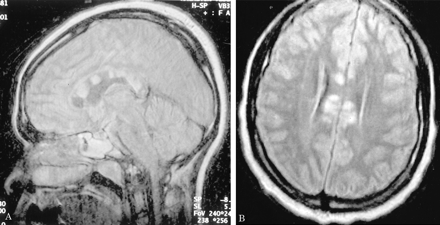

多病灶的幕上的白质病变,包括胼胝体(图1),在所有27个病人,有频繁的参与小脑,中间小脑总花梗,和脑干图1,表)。病变众多,往往是小(3 - 7毫米)但有些小病变成为支流和一些大的(> 7毫米)。19病人实质增强,当明显,导致大脑的粟粒状的外观(图2)。胼胝体的损伤通常是小的,并且涉及中央与周边的相对保留纤维;增强是变量。急性胼胝体的病变(图3)中观察到的活动脑病取而代之的是一个“充满”/穿孔先生出现在后续所有27例(图4),可能代表microinfarctions,没有出现在其他地方。胼胝体,最好在薄片(3毫米厚)矢状T1或T2矢状/质子密度加权图像,由一系列小(3毫米)中央孔相隔7毫米矢状T1和T2矢状/质子密度图像。这些扩展在整个长度的胼胝体。当急性(“雪球”)(见大图3)胼胝体的病变,慢性残余孔较大,尤其是在压部。线性缺陷有时看到的,可能反映microinfarction间接辐射在胼胝体轴突。中央孔(见图4)被认为是由于横向辐射的胼胝体轴突的微型心肌梗塞的可能性。

有深的灰色基底节和丘脑病变19病人(参见表),通常体现在T2信号强度增加,质子密度,和天赋的图像。大病变类似“巨大陷窝”43并建议纹状体外动脉增的广泛参与。三个这样的病人显示这些病变显著增强,伴随着leptomeningeal增强。实质增强(见图2)有关的大脑区域,偶尔与leptomeningeal增强(见相关表)。串行扫描被执行,增强可能是更常见。脑病减弱和病人开始恢复,只有残余病灶中央(见胼胝体的洞图4)和一些白质病变。在两个病人,增加信号强度变化在胼胝体伴随着中央胼胝体的洞在最初的MRI检查。更严重影响病人、脑和小脑萎缩随之而来。在两个这样的实例,胼胝体越来越萎缩,前面提到的胼胝体的洞几乎消失了。

在一些患者中,白质变化是最小的程度与严重程度的脑病。双倍剂量与磁化钆转移可能显示(见更广泛的变化图2),这将有助于解释这个明显的临床/差距先生。我们使用这个序列只在我们的一个病人,然而。